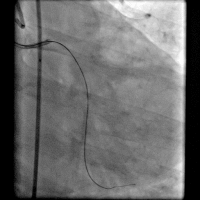

第一次手术过程

手术时间: 入院当天上午4点00分。

术中用药: 术中肝素3000单位。

手术过程(一): 将Runthrough NS 0.014″×180 cm导丝通过右冠病变放到右冠脉后降支远端,沿导丝送入抽吸导管反复抽吸。

手术过程(二): 沿导丝送入EXCEL 2.5×14 mm药物支架一枚至右冠中段,以14 atm×12 s释放。